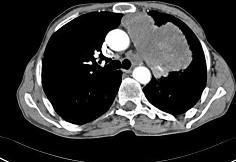

问题 56岁,男,意识错乱情绪不稳定1周,请结合胸片和CT图,选出最可能的诊断 ( )

选项 A.肺癌 B.错构瘤 C.胸内甲状腺肿 D.韦格肉芽肿 E.胸腺瘤

答案 A